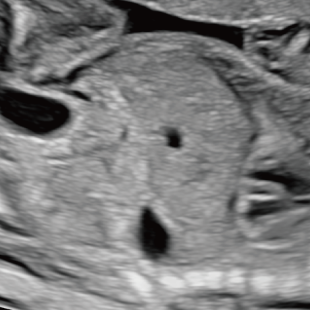

通常の妊婦健診で行う超音波検査では、主に胎児発育(推定体重)、羊水の量、胎児の向きを確認しています。一方で健診の限られた時間内では、胎児を詳細かつ系統的に評価することが難しい場合があります。当院で行っている胎児超音波スクリーニングとは、高性能な超音波検査機器を用いて胎児の発育や形態(からだの構造)をより詳しく観察し、胎児の状態を丁寧に評価する検査です。 出産前に赤ちゃんの状態をより詳しく知りたいという患者さんのご希望にお応えするため、当院では超音波検査士*および超音波専門医・指導医**が胎児超音波スクリーニングを担当します。

Voluson Expert 22®(GEHealthcare)という産婦人科領域におけるハイエンド超音波診断装置を使用しています。 従来機種と比べ、より高精細な画像描出性能と高度な解析機能を備えており、 胎児の発育や形態をより詳細に観察することが可能です。